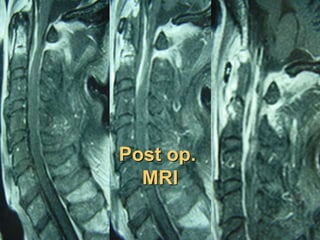

Post op.

MRI

Occipito-cervical

stabilization